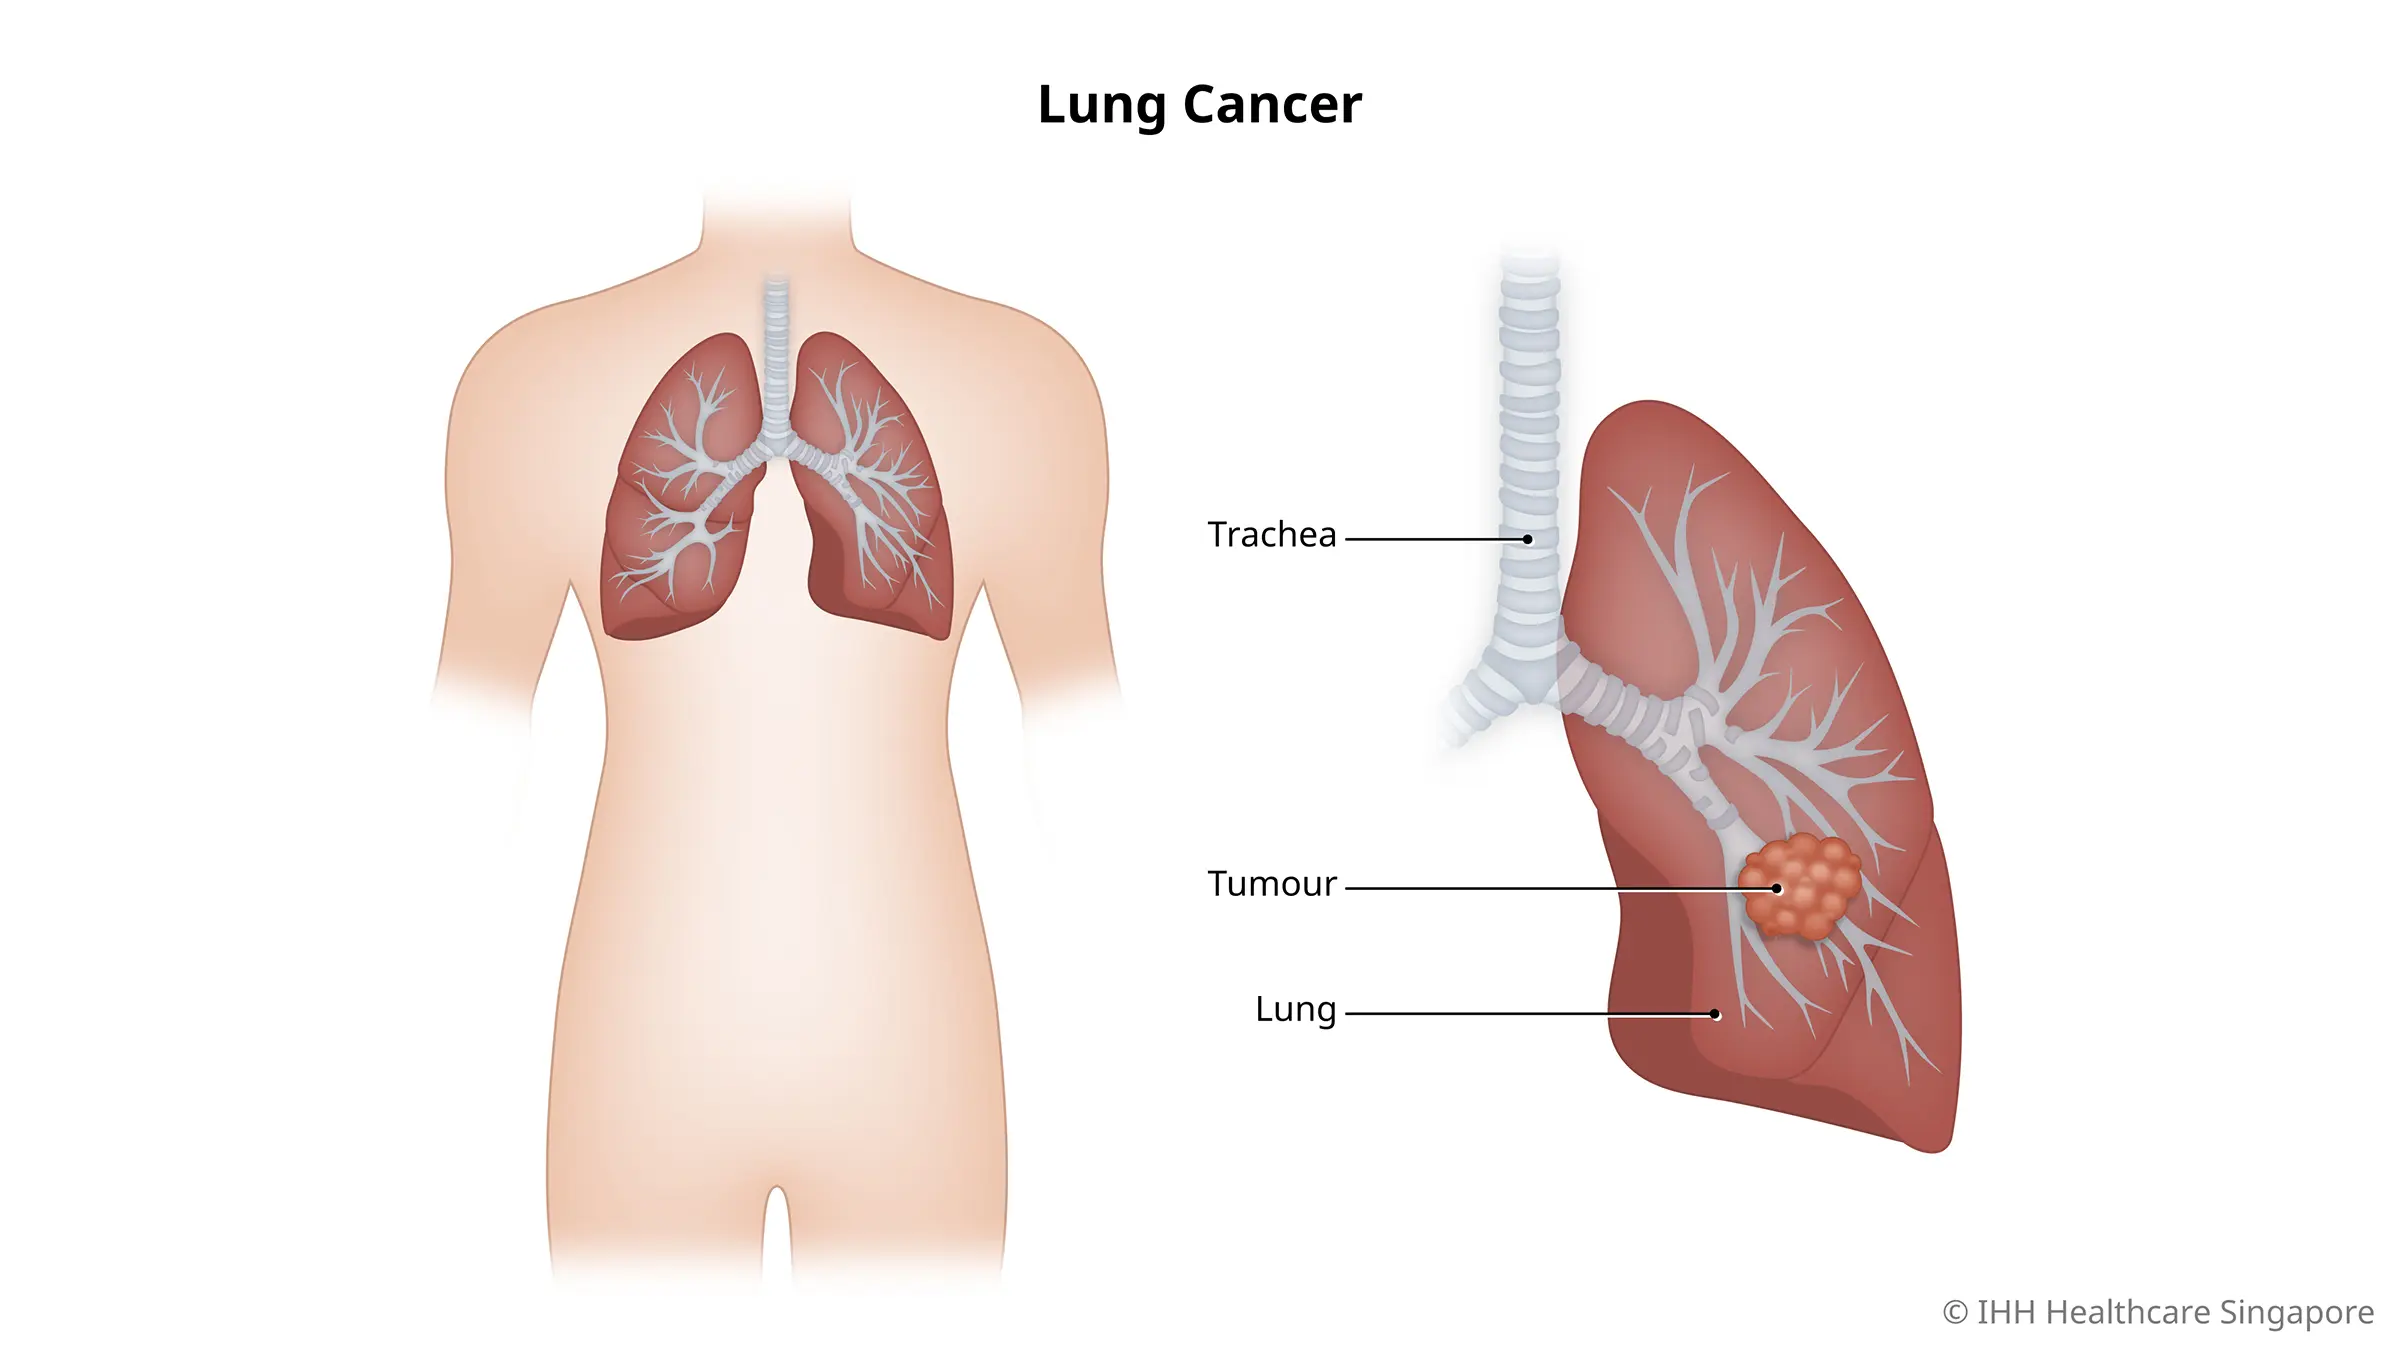

The Stealthy Onset of Lung Cancer

Lung cancer often begins its assault quietly, with subtle symptoms or no symptoms at all in the early stages. Ignoring lung cancer health warnings, such as persistent cough, shortness of breath, or unexplained weight loss, allows the disease to advance unnoticed. Recognizing the stealthy onset is vital for timely intervention.

The Aggressive Nature of Lung Cancer

Lung cancer is notorious for its aggressive nature, often diagnosed at advanced stages when treatment options become limited. Neglecting lung cancer health warnings can allow the disease to progress rapidly, making it challenging to achieve favorable outcomes. Understanding the aggressive nature of lung cancer underscores the urgency of proactive measures.

Impact on Overall Health and Well-being

The consequences of neglecting lung cancer health extend beyond the lungs. The disease can metastasize to other organs, affecting overall health and well-being. Ignoring these warnings may result in complications that impair various bodily functions. Acknowledging the systemic impact reinforces the need for comprehensive lung cancer management.